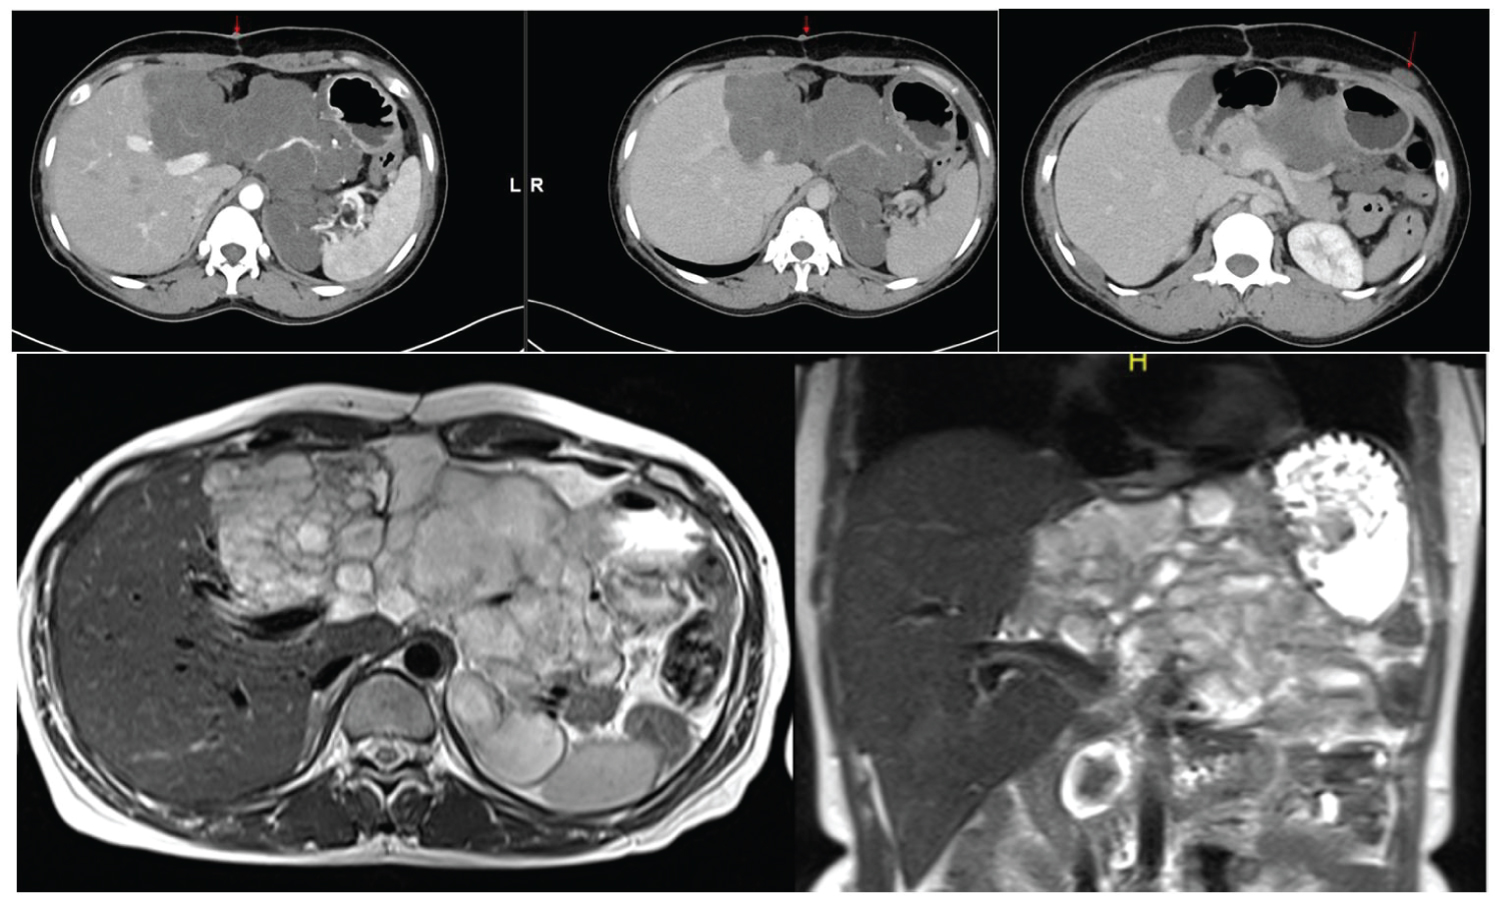

Our patient is a middle aged female who is a known retro positive case and not taking medications for past one year, now presented with abdominal pain, significant weight loss and upper abdominal swelling for 3 months. CECT shows an irregular heterogeneously enhancing exophytic mass lesion arising from right lobe of liver with central necrosis and abdominal lymphadenopathy (Figure 1).

Figure 1: Hepatic lymphoma. (a,b) Contrast enhanced CT coronal and axial sections shows an irregular heterogeneously enhancing exophytic mass lesion arising from right lobe of liver with central non-enhancing hypodense areas (necrosis). Multiple heterogeneously enhancing mesenteric, para aortic and left external iliac lymph nodes seen (⋆ red star). Moderate ascites present. View Figure 1